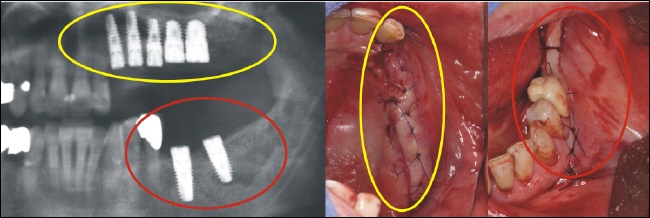

Implantation

Im Oberkiefer (gelber Kreis) und im Unterkiefer (roter Kreis) wurden die fehlenden Zähne durch Implantate ersetzt. Auf den rechten Bildern sieht man, dass die Zähne geschlossen, also geschützt unter der Schleimhaut, einheilen.